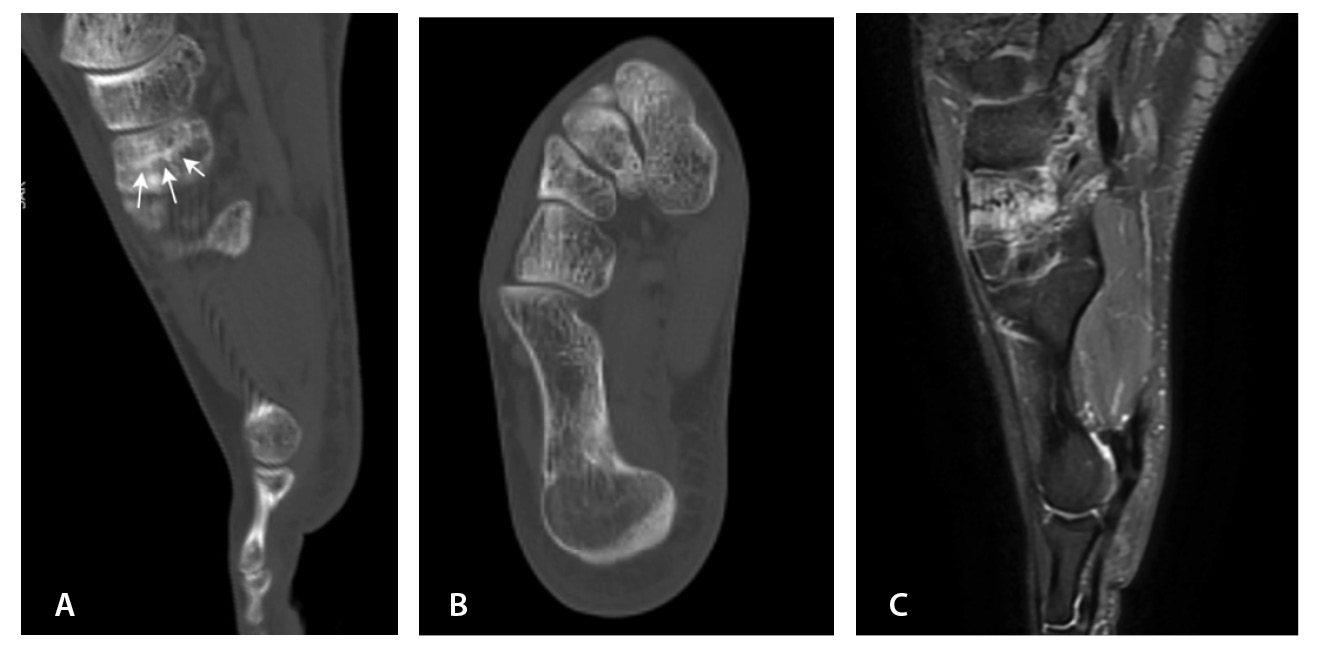

Переломы без смещения фрагментов, а также краевые и авульсионные переломы не всегда четко визуализируются на рентгенограммах из-за суперпозиции теней, наличия фиксирующих шин и гипсовых повязок, которые накладываются на зону интереса. При клинических признаках перелома и рентгеннегативной картине у таких пациентов КТ имеет большую диагностическую значимость (рис. 2).

Рис. 2. Рентгеннегативный перелом дистального метадиафиза большеберцовой кости 2-го типа по Солтеру – Харрису (стрелки) у мальчика 11 лет: А, Б – рентгенография; В – компьютерная томография (КТ), корональная плоскость; Г – КТ, сагиттальная плоскость; Д – КТ, аксиальная плоскость